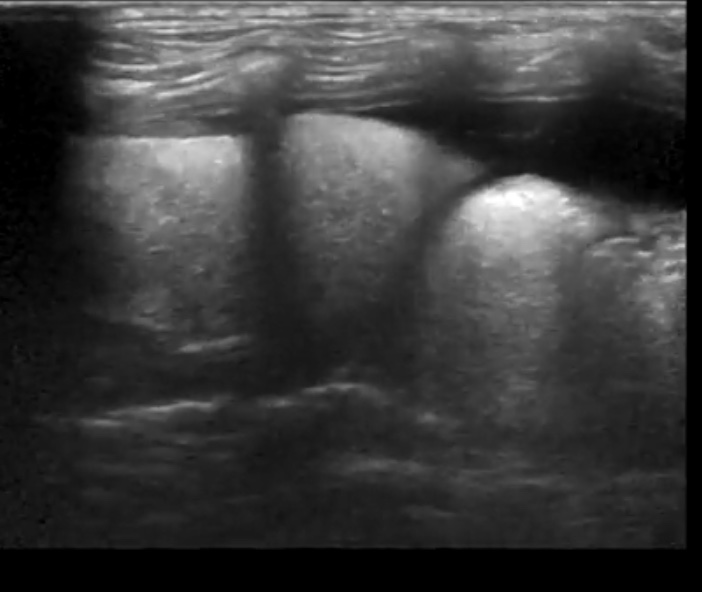

Возможности УЗИ органов грудной полости ограничены из-за узких межреберных промежутков. Ребра представляют собой костные структуры, не пропускают УЗ луч, создают акустическое затемнение. Легкие наполнены воздухом, поэтому их визуализация так же затруднительна (воздух является плохим проводником УЗ луча).

В грудной полости находятся два листка плевры: костальная и висцеральная (покрывает легкие). Между ними есть пространство, заполненное незначительным количеством жидкости, что позволяет листкам плевры свободно скользить относительно друг друга при дыхании.